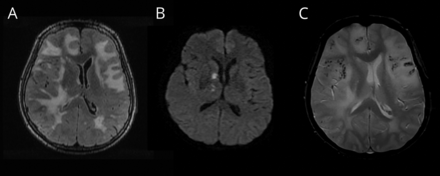

一个减轻以往健康的60岁的女人插管头痛和个月历史的帷幕,历史的记忆丧失。MRI进行(图1)。数字减影血管造影的头,水痘一带状疱疹病毒PCR,免疫球蛋白G CSF,肝炎B / C, CSF隐球菌抗原,艾滋病毒、莱姆血清学和梅毒屏幕是负的。最初的鉴别诊断包括中枢神经系统血管炎和颅内淋巴瘤。她被诊断出患有炎症基于clinicoradiologic标准脑淀粉样血管病(敏感性为82%,特异性为97%),1梗死认为amyloid-β-related脉管炎亚型。几天之内的类固醇,她完全清醒,重复MRI 5个月后显示改善脑白质病(图2)。蒙特利尔认知评估分数23/30开始后的两周治疗和22/30 5个月后。

图1

最初的核磁共振

(一)t2加权融合性的脑白质病扩展到皮层下白质质量效应。(B) Diffusion-weighted成像10天后变化对表观扩散系数序列相关(见图)与梗塞是相一致的。(C)梯度回波序列显示microhemorrhages。